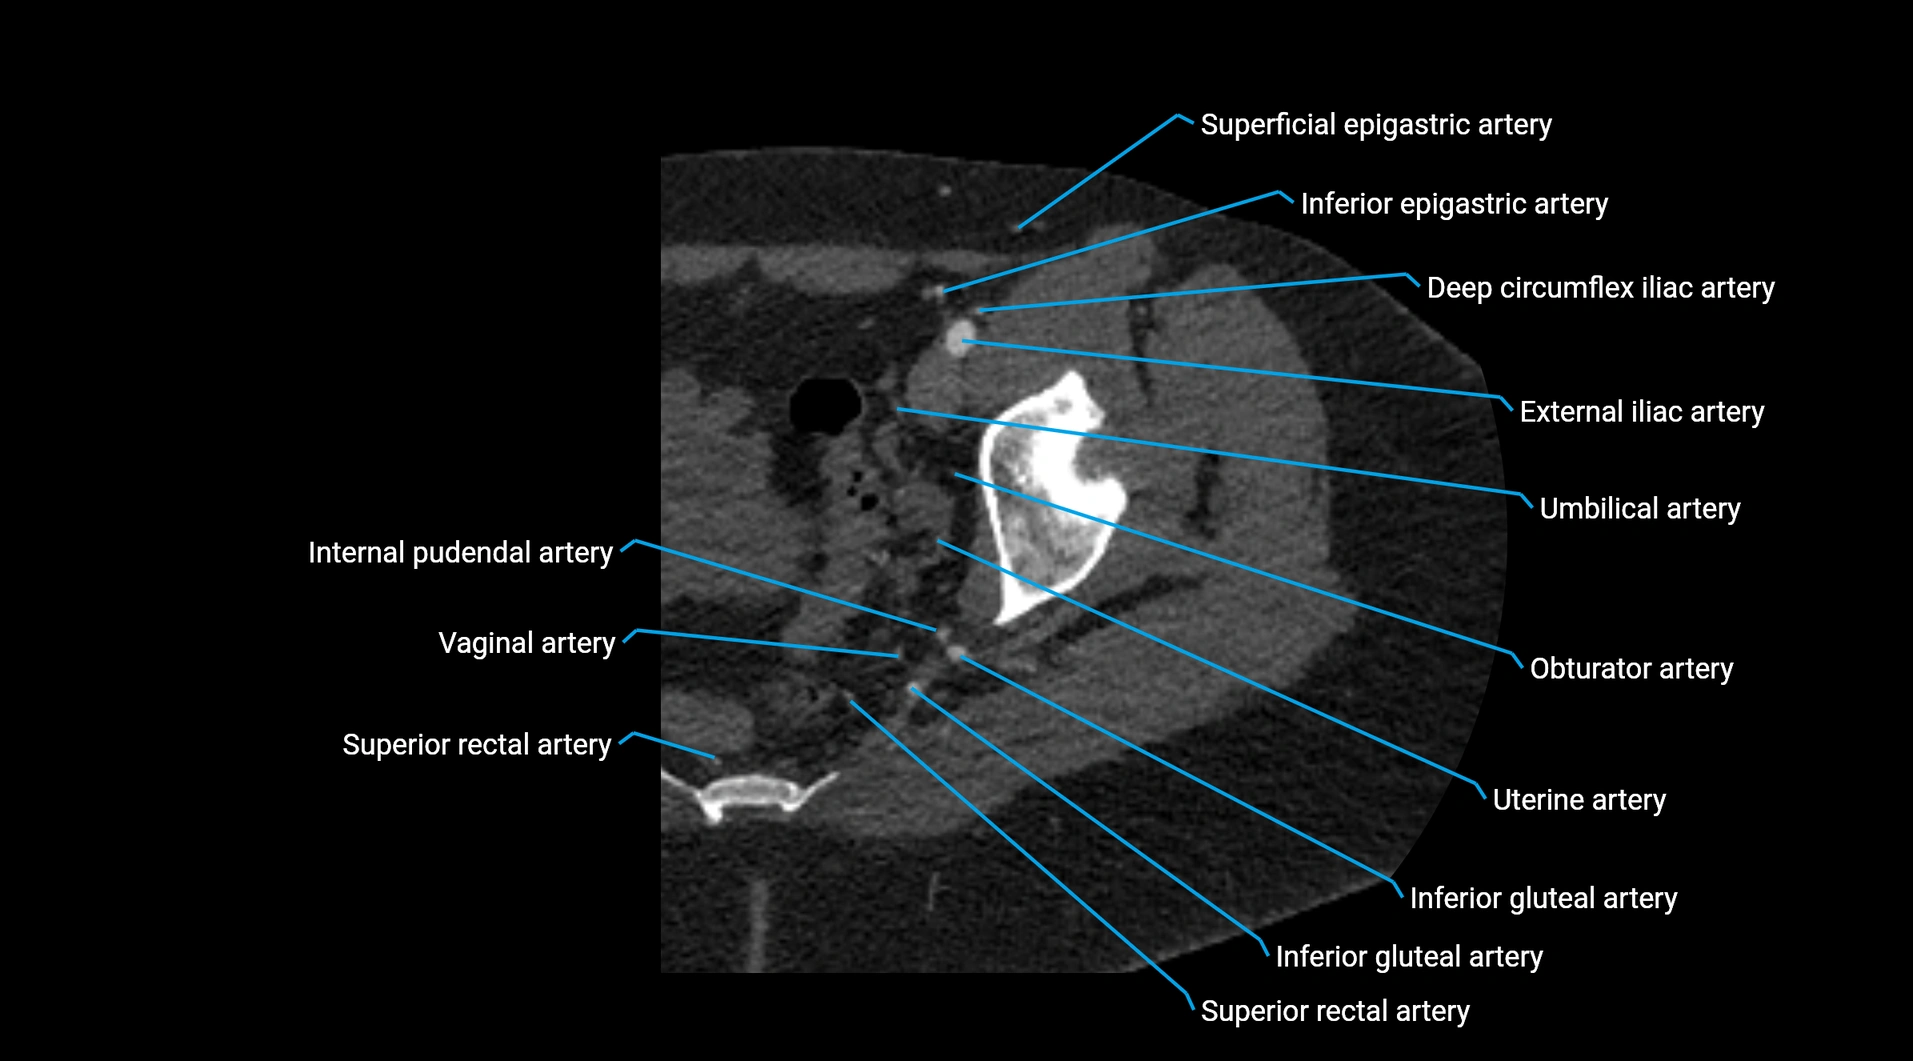

Contrast-enhanced CT (CTA):

• Gold standard for abdominal aortic imaging

• Provides excellent detail of lumen, wall, aneurysm, thrombus, and branch vessels

• Multiplanar and 3D reconstructions help in aneurysm measurement, stent graft planning, and dissection evaluation